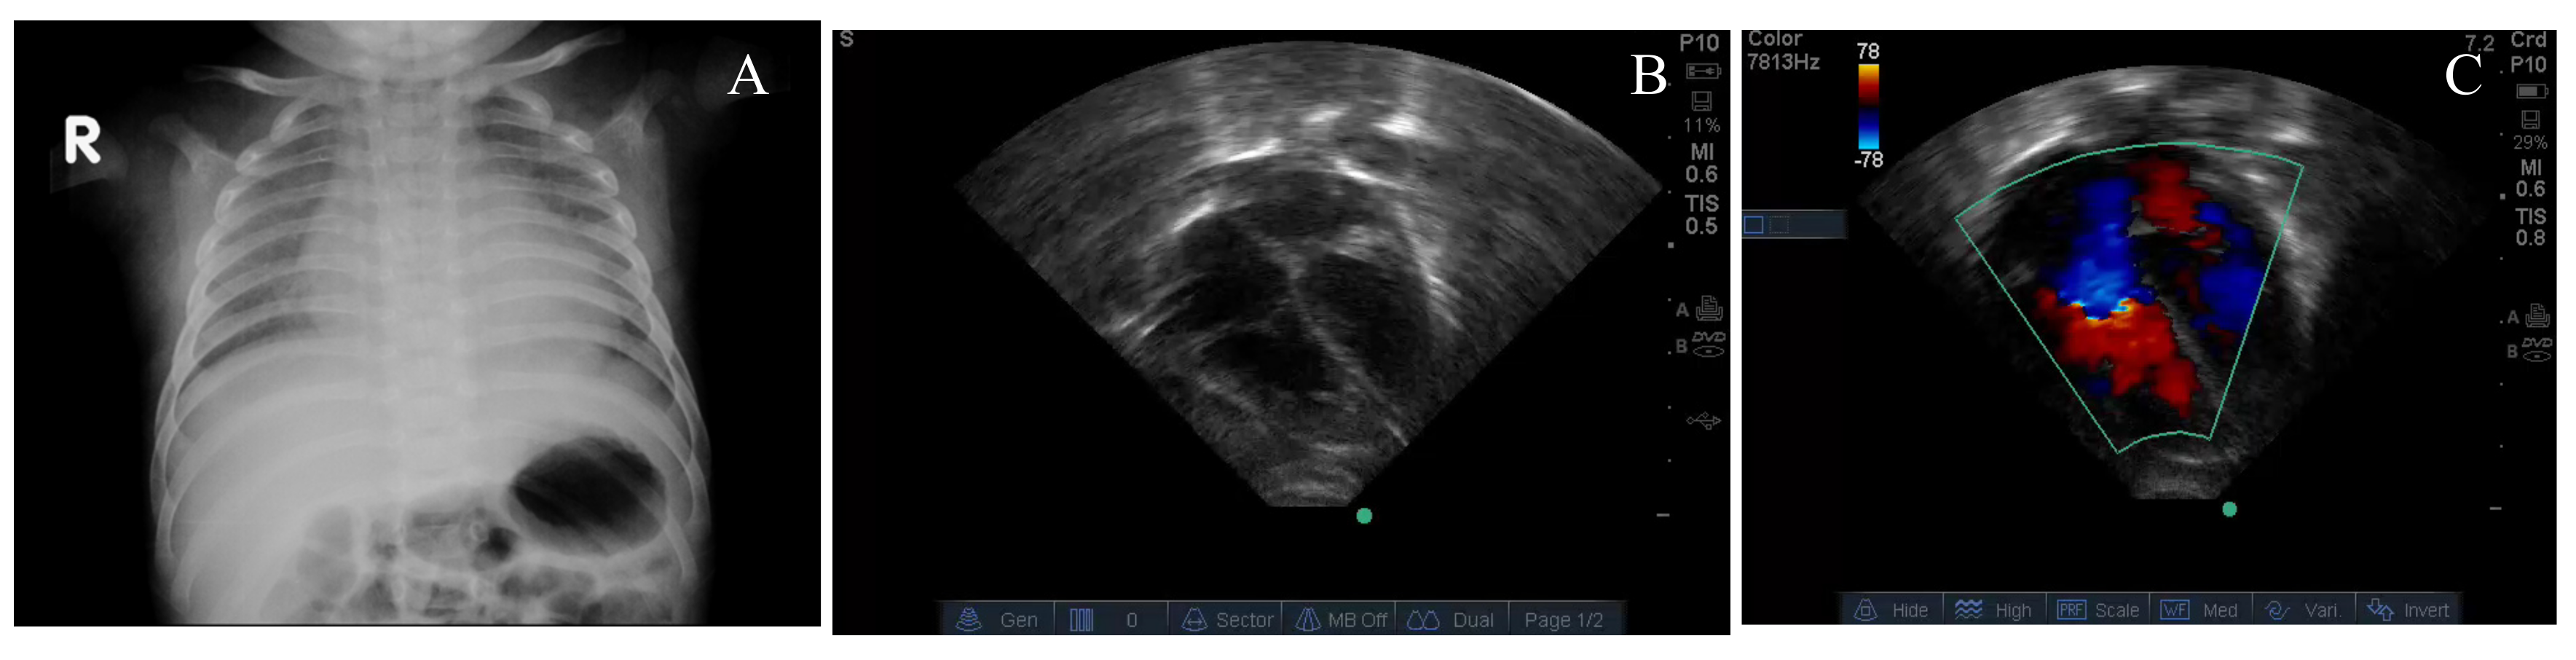

| Case 1 | Case 2 | Case 3 | Case 4 | |

|---|---|---|---|---|

| Age at presentation | 2 months | 3½ months | 2 months | 3 months |

| Gender | Male | Male | Male | Male |

| Birth weight | 3.2 kg | 3.0 kg | 2.9 kg | 2.5 kg |

| Current weight | 4.7 kg | 5.6 kg | 4.1 kg | 4.7 kg |

| Consanguinity | No | No | Yes | Yes |

| Family history of similar illness | - | - | Brother died at 3 months | Sister died at 3½ months |

| Initial symptoms and signs | fever, cough, runny nose, respiratory distress, stridor, and irritability | feeding difficulty, cough and worsening respiratory distress | respiratory arrest and intubated in community hospital | fever, lethargy, respiratory distress |

| Maternal/infant diet | Polished, washed, white rice/exclusive breastfeeds | Polished, washed, white rice/exclusive breastfeeds | Polished, washed, white rice/exclusive breastfeeds | Polished, washed, white rice/exclusive breastfeeds |

| Hepatomegaly (cm below costal margin) | 3 cm | 2 cm | 2 cm | 3 cm |

| Worst pH | 6.98 | 7.08 | 7.09 | 6.92 |

| Highest lactate (mM/L) | 9.8 | 6.8 | 8.5 | 16.4 |

| Lowest PaO2/FiO2 | 40 mmHg | 65 mmHg | 35 mmHg | 55 mmHg |

| Peak estimate of RVSP (mm Hg) | 82 | 74 | 60 | 67 |

| Ventilation mode High frequency ventilation (HFV) or Conventional mechanical ventilation (CMV) | HFV | HFV | HFV | CMV |

| Pulmonary vasodilators | Nitric oxide (NO) | NO Sildenafil | Sildenafil Bosentan | - |

| Circulatory support | Milrinone Epinephrine Vasopressin Norepinephrine | Epinephrine Milrinone | Dopamine | Dopamine Furosemide |

| Thiamine level (infant/mother) (normal—66.5 to 200 nM/L) | 10 (infant) | 12.46 (infant) 2.38 (mother) | 3.7 (infant) 4.2 (mother) | 75 (mother) |

| Response to thiamine (hours or days after first infusion) | ||||

| Extubation | 3 days | 40 h | 34 h | 36 h |

| Wean to room air | 5 days | 4 days | 4 days | 3 days |

| Resolution of PH by echocardiogram after thiamine | Improvement started by 4 h, resolution by 5 days. | Improvement by 3 h, resolution by 6 days. | Improvement started by 8 h, resolution by 7 days. | Resolution 5 days. |